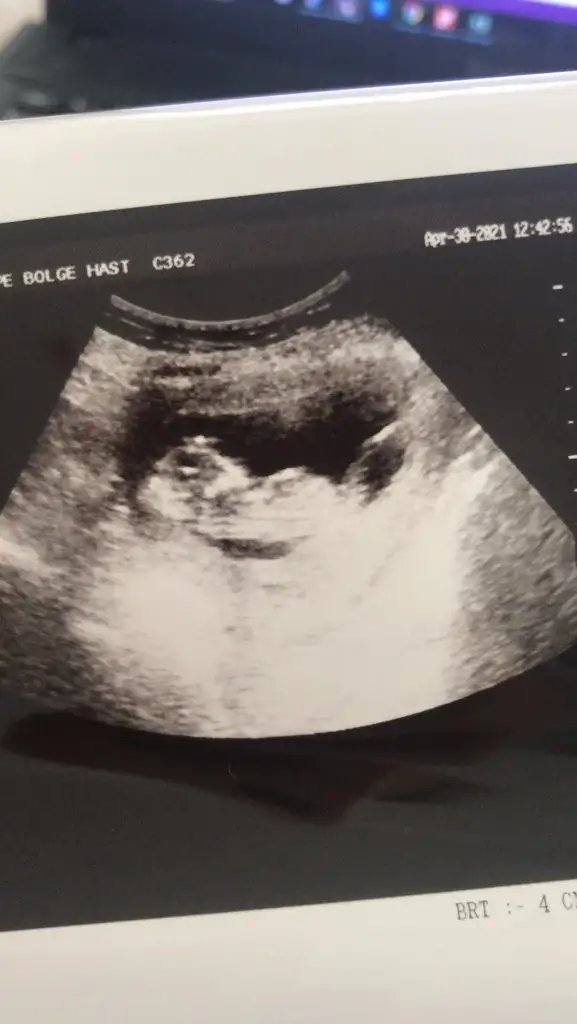

dr soylemeden siz gorun genital nub teorisi ( bebegin cinsiyeti)

14+3 tahminde bulunurmusunuz🤦‍♂️

Eklentiler

• USER_SCOPED_TEMP_DATA_MSGR_PHOTO_FOR_UPLOAD_1619699855146_6793513581238554568.webp

USER_SCOPED_TEMP_DATA_MSGR_PHOTO_FOR_UPLOAD_1619699855146_6793513581238554568.webp

16,7 KB · Görüntüleme: 69